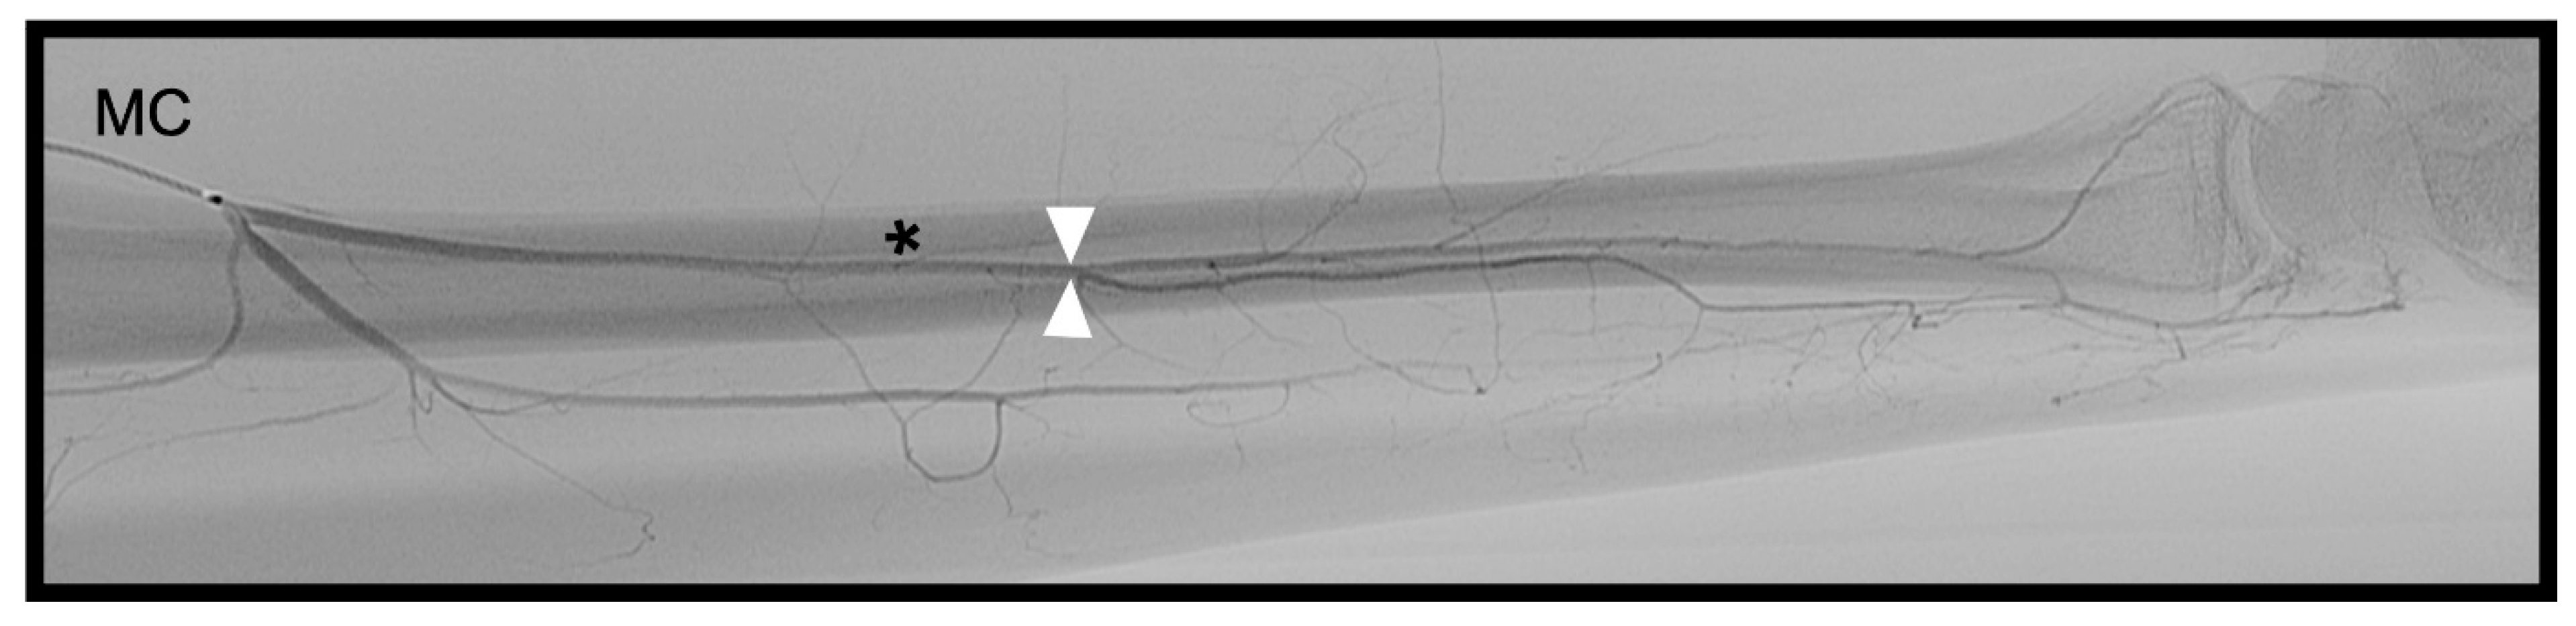

3.3. Anterior Interosseous Artery (AIA)